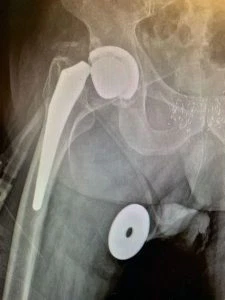

Plain film radiographs revealed thinning and “penciling” of the neck of the femoral component, indicating likely fretting corrosion at the trunion – also known as “trunnionosis”. In fact the radiographs suggested the trunion had become so corroded that it had fractured. Further inquiry revealed the type of component used in the initial replacement surgery has since been shown to suffer from this phenomenon at a higher rate than others – though this was not known at the time.

We utilized the same surgical approach as the previous surgeon used – in this case the lateral approach – and exposed the hip joint in a careful and meticulous fashion. Once this was completed, we dislocated hip and retrieved the femoral head component which revealed that the neck of the femoral component had been pistoning within the head component, leading it to have become eroded down to resemble the tip of a pencil.